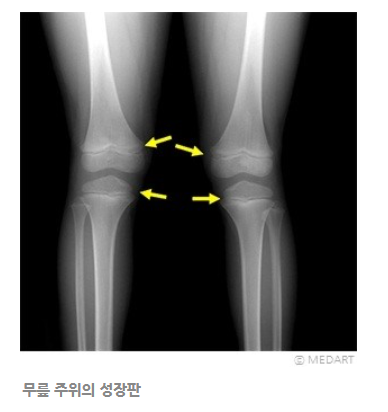

성장판은 부드러운 연골세포로 돼어 있다고 합니다.

이곳의 연골세포가 증식, 성숙, 석회침착, 모세혈관 침투, 뼈 침착과정이 일어나면서 뼈의 길이성장이 이루어 지는 것이라고 합니다.

아이들의 성장 지표가 되는 키는 성장호르몬이 관절 부위인 뼈의 양쪽 끝부분에 붙은 성장판 세포를 자극 증식시키면서 자라게 된다고 합니다.

성장판이 있는 부위

어깨, 팔꿈치, 손목, 척추, 골반, 대퇴골, 정강이뼈, 발목, 발뒤꿈치, 손가락, 발가락 등 모든 긴뼈의 양 끝에 있다고 합니다.

손목, 팔꿈치, 고관절 등의 X선 촬영을 하여 성장판 상태를 확인하는데 초등학생은 보통 손목 사진을 찍어 알 수 있다고 합니다.